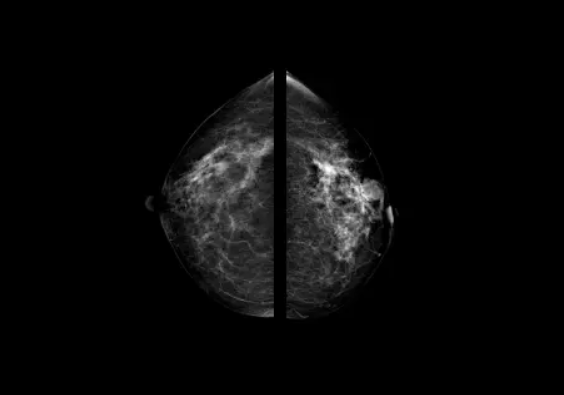

Снимки, получаемые с помощью искусственного интеллекта DIAR-MAMMO

Программное обеспечение использует интеллектуальные алгоритмы нейронных сетей и эффективный приемник для анализа получаемых геометрических данных о размере, плотности и оптимальной компрессии молочной железы, благодаря чему полученные изображения позволяют увидеть мельчайшие очаги поражения ткани молочной железы.

Система определяет плотность ткани молочной железы по АСВ и присваивает исследованию категорию ВI-RADS.